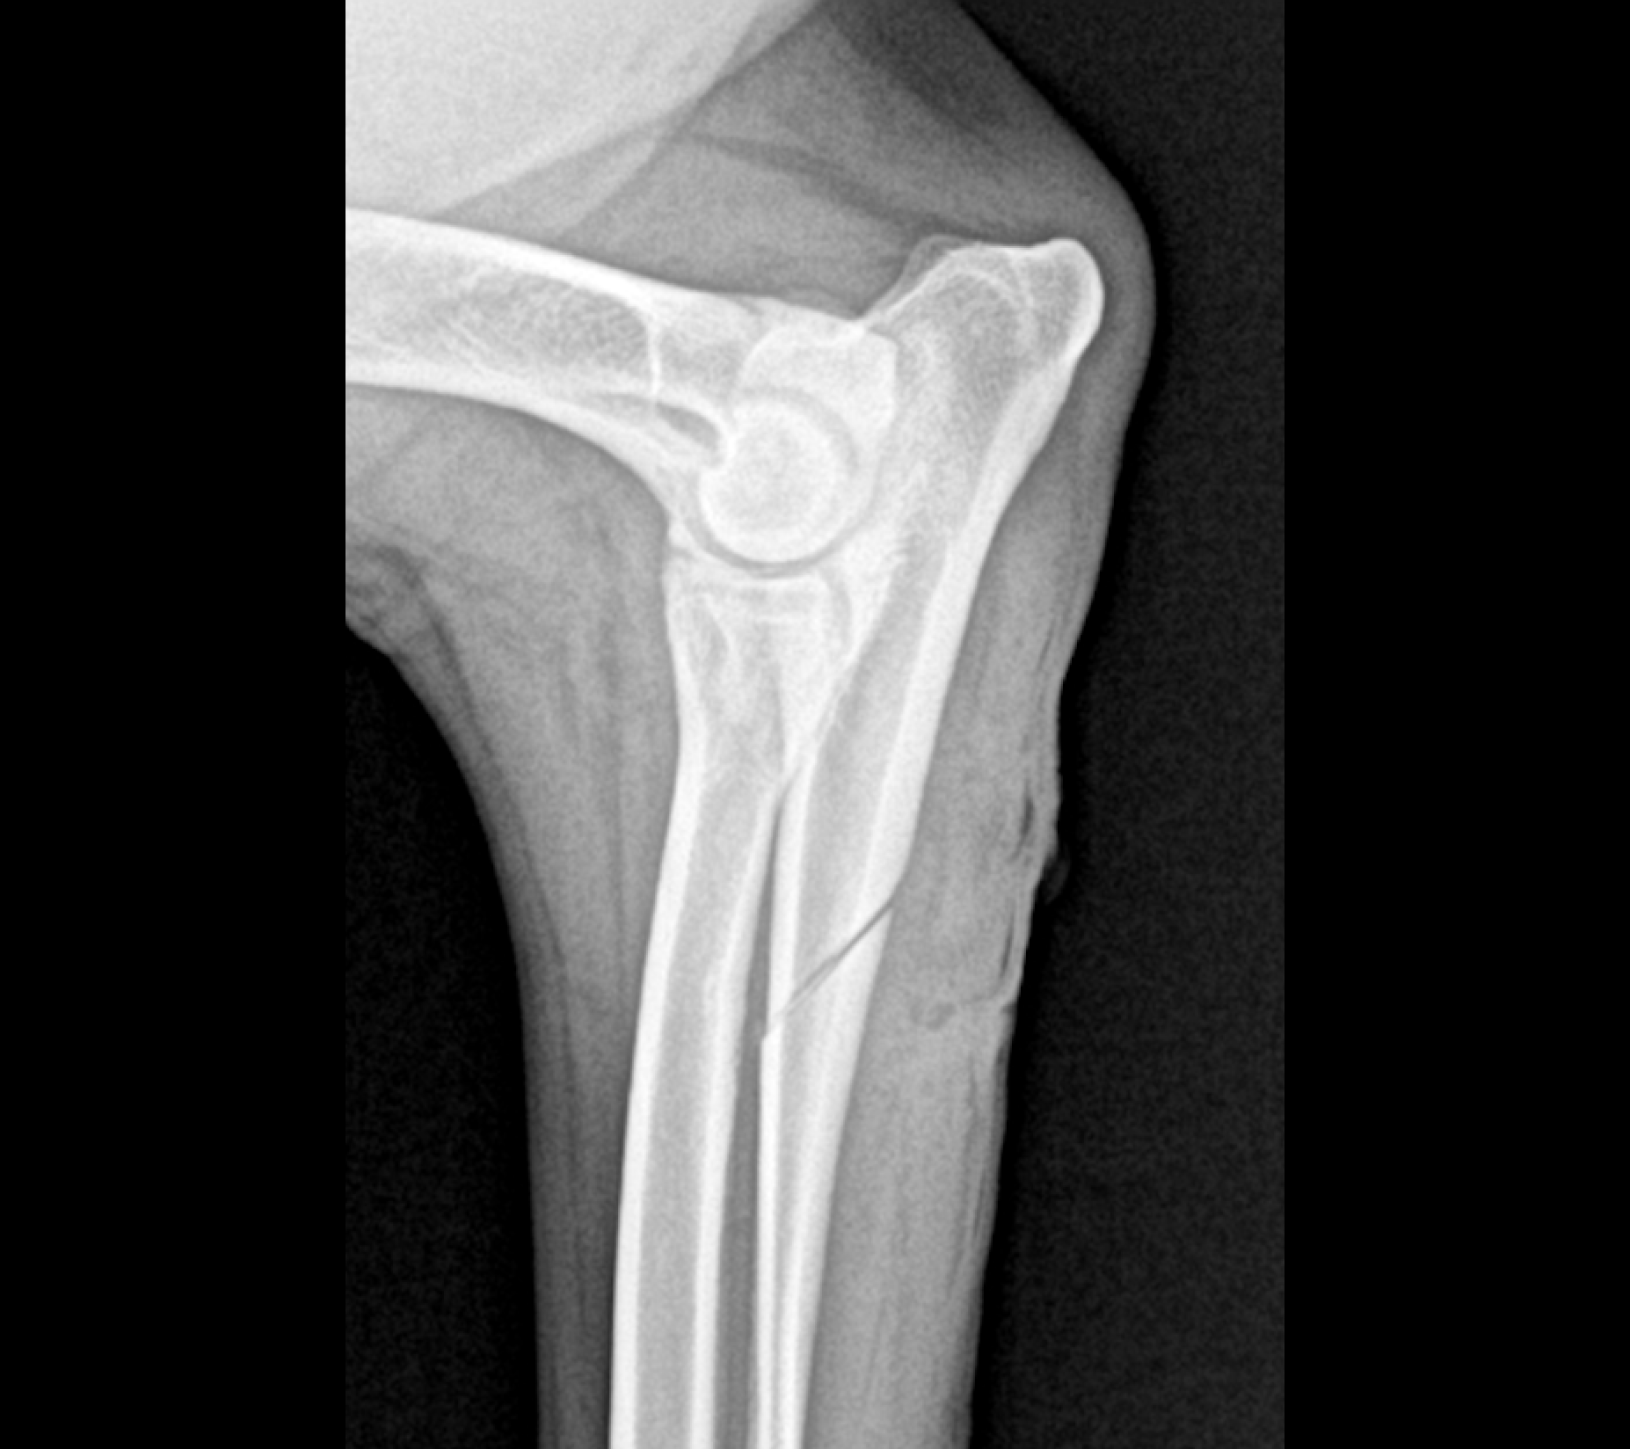

Los Rayos X pueden mostrar anormalidades en la congruencia articular y cambios óseos asociados a la displasia de codo. Sin embargo, existe superposición de estructuras óseas en las proyecciones convencionales, limitando la detección de alteraciones.

La Tomografía computerizada (CT) o TAC es la técnica por imagen de elección. El procesado avanzado de la imagen nos permitirá visualizar finos cortes de la anatomía y detectar pequeñas lesiones (por ejemplo, fragmentación del proceso coronoides), las cuales son difíciles de diagnosticar en radiografías convencionales.